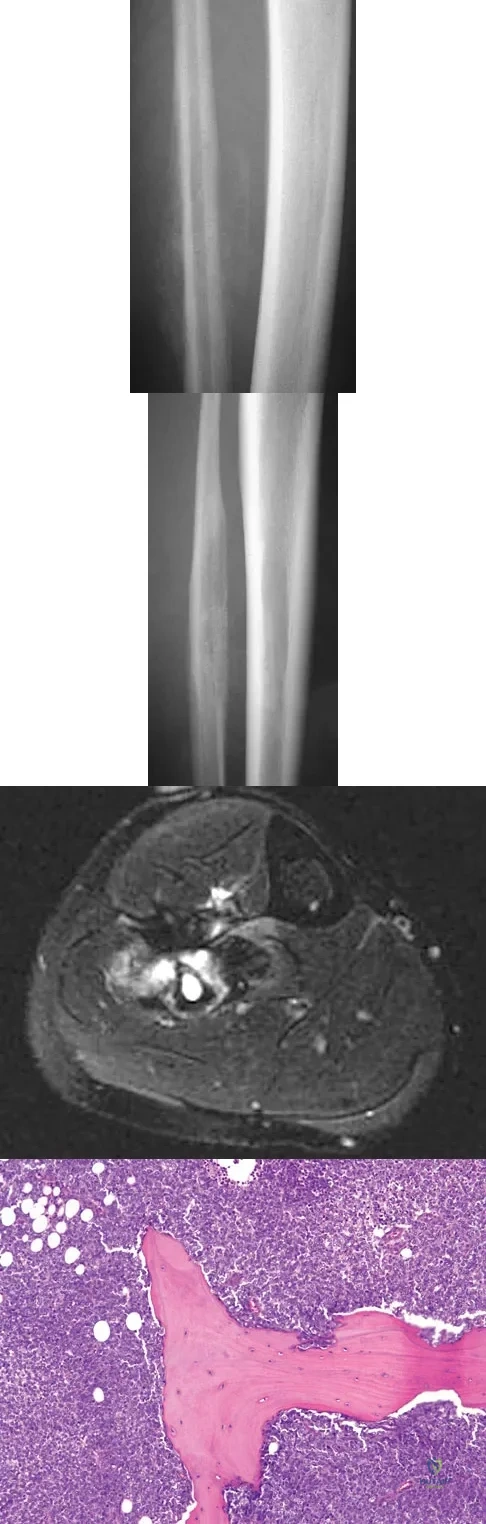

A 20-year-old patient has foot pain. A radiograph and T1-weighted MRI scan are shown in Figures 8a and 8b. A biopsy specimen is shown in Figure 8c. Treatment should consist of